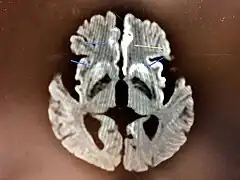

Magnetic resonance image of sporadic CJD[2]

Through the image of MRI, the obvious precipitation of prion protein in the brain is visible.

• MRI of the brain – often shows high signal intensity in the caudate nucleus and putamen bilaterally on T2-weighted images.